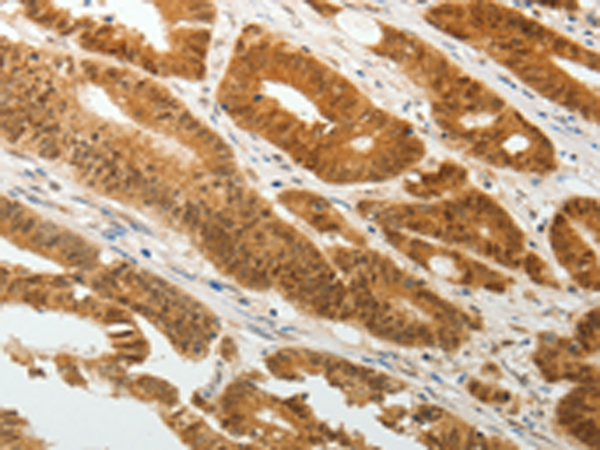

分类: 科研抗体货号: P11131别名: SELS; VIMP; ADO15; SBBI8; SEPS1; AD-015应用: IHC反应种属: Human, Mouse, Rat